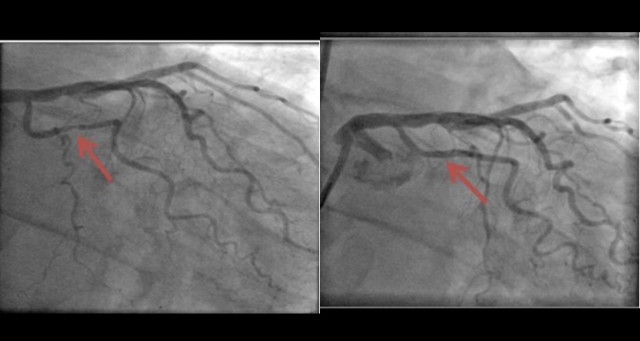

Высокотехнологичная медицинская помощь оказана 56-летнему псковичу по федеральной квоте. «Было сделано стентирование двух сосудов сердца. Операция прошла успешно, состояние больного удовлетворительное. Вчера мужчину выписали», — сообщил кардиохирург Федерального центра высоких медицинских технологий Михаил Исаян.